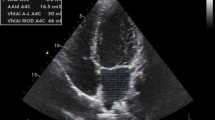

Echocardiography

Echocardiography including two-dimensional, motion mode, and color Doppler was conducted. The following measurements were used for LV mass: left ventricular cavity diameter in diastole (LVIDd), interventricular septum thickness in diastole (IVSd), and LV free wall thickness in diastole (LVFWd) using the following equation: LVmass = 1.04 × ((LVIDd + LVFWd + IVSd)3 − LVIDd3) − 13.6 that has been validated in horses [36]. Left atrial diameter (LADiameter) was measured during maximal diameter measurement just prior to mitral valve opening as previously described [37]. Left atrial area (LAArea) was measured at three different time points: LAAmax = 1 frame before mitral valve opening, LAAa = at onset of P wave, and LAAmin = at mitral valve closure. LV mass was directly corrected for BW [29], and LADiameter and LAArea were corrected using allometrical scaling to BW 500 kg using the following equations: LADiameter(500) = measured LADiameter / BW1/3 × 5001/3 and LAArea(500) = measured LAArea / BW2/3 × 5002/3 [38]. Left atrial function was assessed as previously described [37], including the overall LA fractional area change (LA-FACtotal = (LAAmax − LAAmin) / LAAmax). LA-FACpassive = (LAAmax − LAAa) / LAAmax representing the passive atrial emptying during early diastole and diastasis. LA-FACactive = (LAAa − LAAmin) / LAAa representing the active atrial contraction.

Trained horses had significantly larger hearts (mean weight/BW: 0.90 ± 0.05%, n = 9) compared to untrained animals (mean weight/BW: 0.81 ± 0.09%, p = 0.01, n = 7). Echocardiographic analysis revealed a significantly larger LV mass in trained animals but no difference in LA dimension or function (Table 1). When comparing LA variables to existing reference values [38], 2/11 trained horses had a LADiameter above the upper limit compared to the general population, as opposed to 0/11 in the untrained group. No correlation between LA size and AF duration was identified.